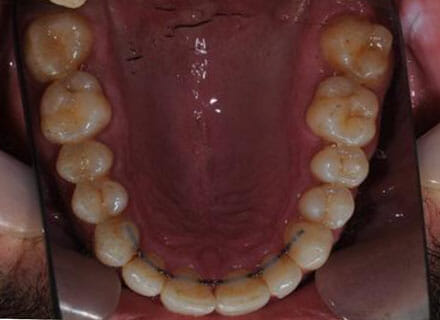

Big gaps and missing back teeth

This is a case where orthodontics and dental implants were used. First we closed the big gaps at the front using a fixed clear brace (this took under 12 months. Then we added 2 new teeth on the lower right where the premolar and molar were decayed right through using dental implants. Here the after pics were taken before the new implant teeth were added lower right.